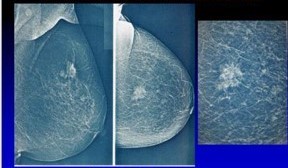

Figura 7 – Xeromamografia

As imagens da xeromamografia eram impressas em papel especial, sendo empregado um toner azul como nesse caso de câncer de mama.